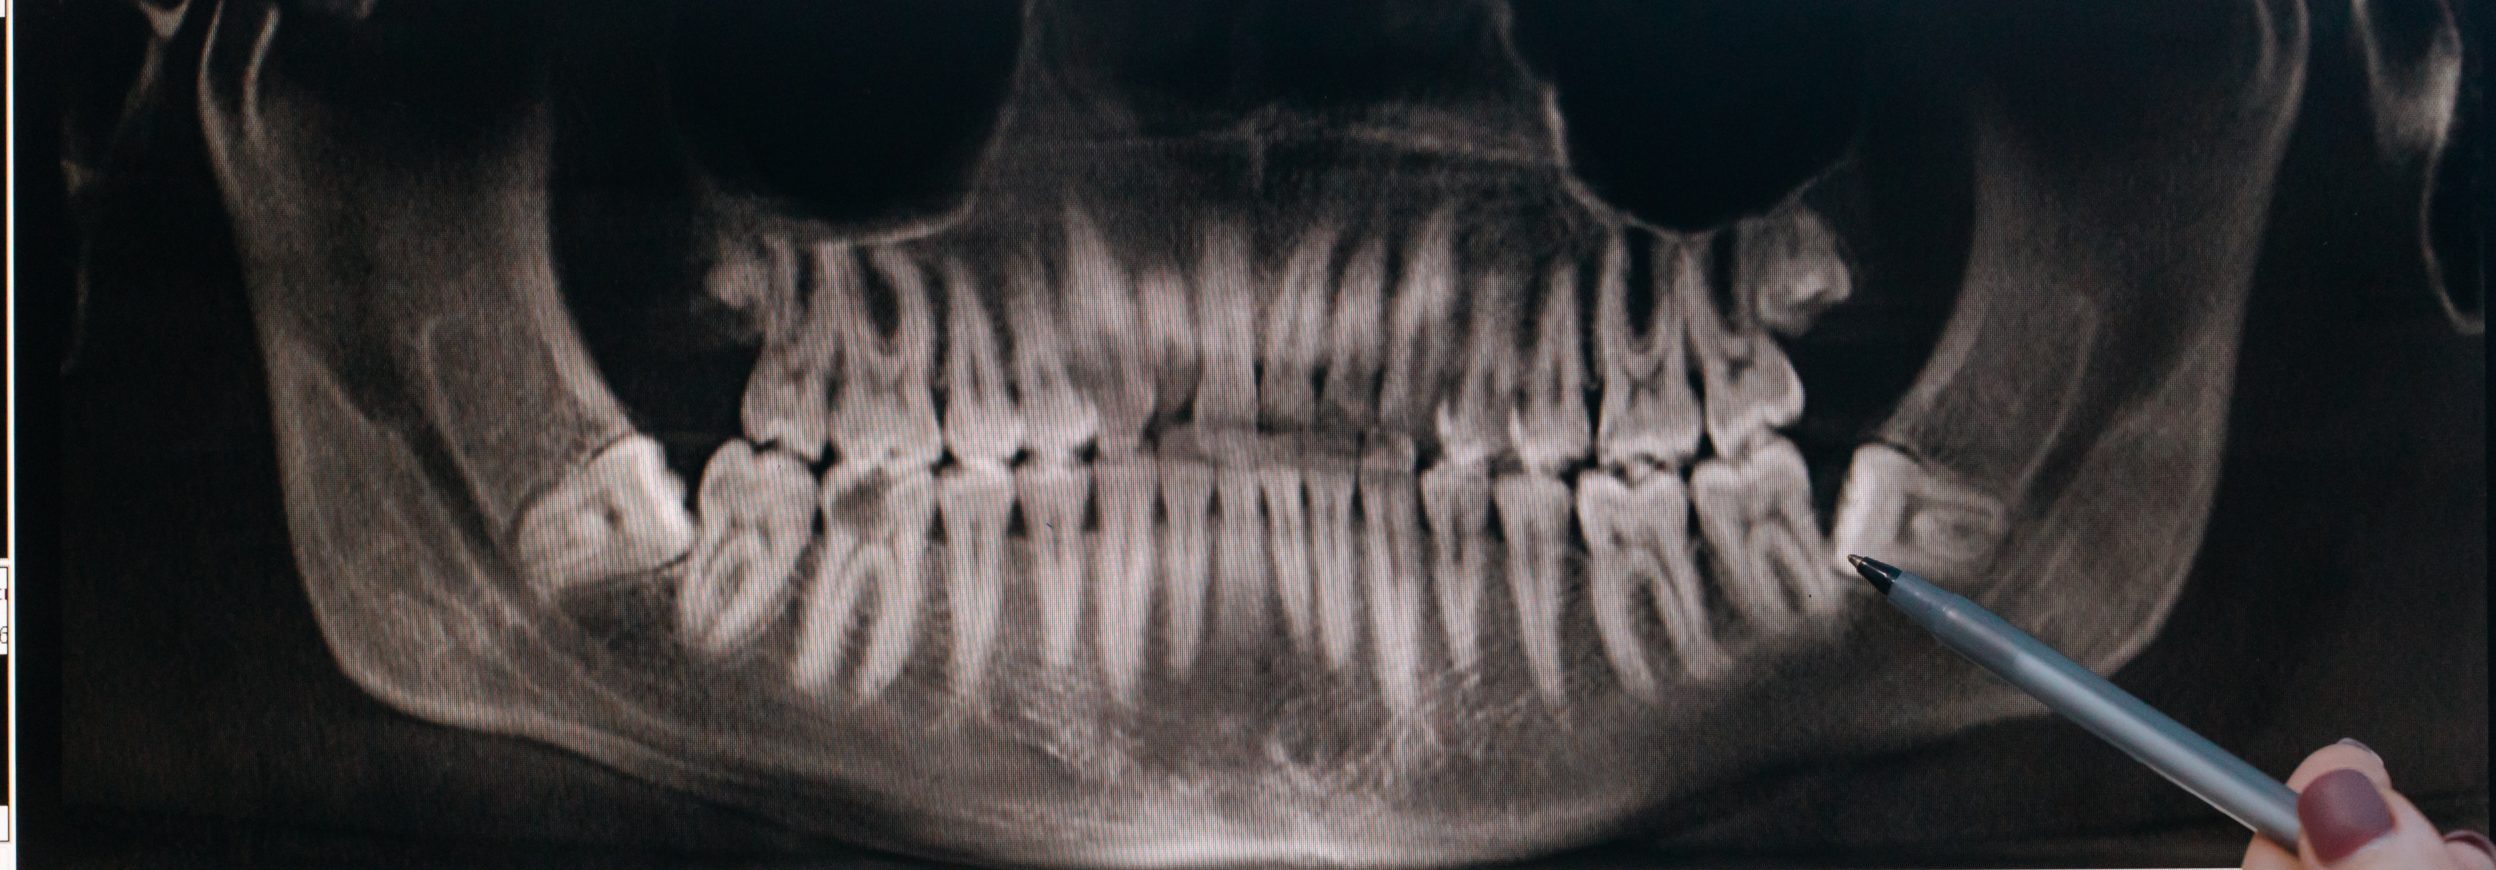

A extração de Dente do siso, ou terceiro molar, é muito comum nos consultórios odontológicos. No entanto, este processo envolve

Dente do siso ou dente do juízo. Muitos ouvem falar dele, mas nem todo mundo sabe para que serve. Por